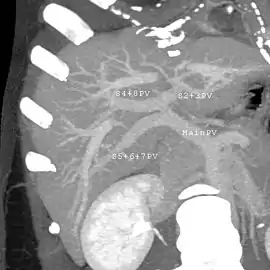

Couinaud classification system

Shape of human liver in animation, with eight Couinaud segments labelled

In the widely used Couinaud system, the functional lobes are further divided into a total of eight subsegments based on a transverse plane through the bifurcation of the main portal vein.[28] The caudate lobe is a separate structure that receives blood flow from both the right- and left-sided vascular branches.[29][30] The Couinaud classification divides the liver into eight functionally independent liver segments. Each segment has its own vascular inflow, outflow and biliary drainage. In the centre of each segment are branches of the portal vein, hepatic artery, and bile duct. In the periphery of each segment is vascular outflow through the hepatic veins.[31] The classification system uses the vascular supply in the liver to separate the functional units (numbered I to VIII) with unit 1, the caudate lobe, receiving its supply from both the right and the left branches of the portal vein. It contains one or more hepatic veins which drain directly into the inferior vena cava.[28] The remainder of the units (II to VIII) are numbered in a clockwise fashion:[31]